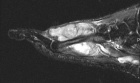

21 year old male with swelling and pain in left foot for six months

Zoom image: Radiological image Radiological image.